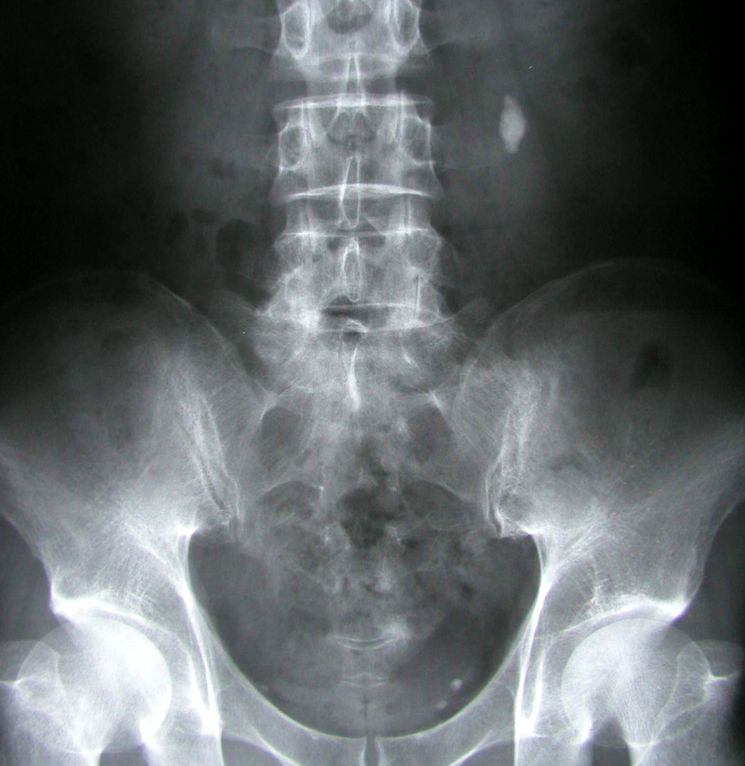

Человек имеет две почки, которые очищают кровь, обеспечивают водно-соляной баланс и отфильтровывают продукты жизнедеятельности организма. Твердые кристаллы в почках могут образовываться из солей и минералов, присутствующих в крови. Довольно часто кристаллы имеют маленький размер и самостоятельно безболезненно выходят из организма. Тем не менее, они могут накапливаться внутри почек и вызывать уролитиаз, то есть мочекаменную болезнь.

Уролитиаз — мочекаменная болезнь может возникать у людей практически в любом возрасте, хотя статистика сообщает, что наиболее часто песок в почках появляется в возрасте с 20 до 50 лет. Обструкция мочеточника песком и камнями проявляется обычно острой спастической болью в поясничной области, тошнотой, рвотой, кровью в моче и др симптомами.